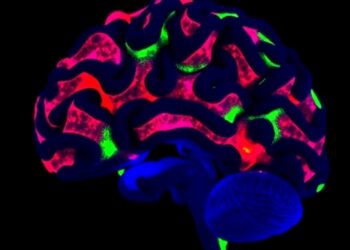

Visual Cues Shape Brain Networks After ACL Surgery

In an era where sports science and neurorehabilitation increasingly intersect, a groundbreaking study published in Scientific Reports is reshaping our...

Real-Time Brain Monitoring Enables Earlier Detection of Infections

A pioneering research initiative led by the University of Waterloo has unveiled an innovative monitoring system poised to revolutionize the...